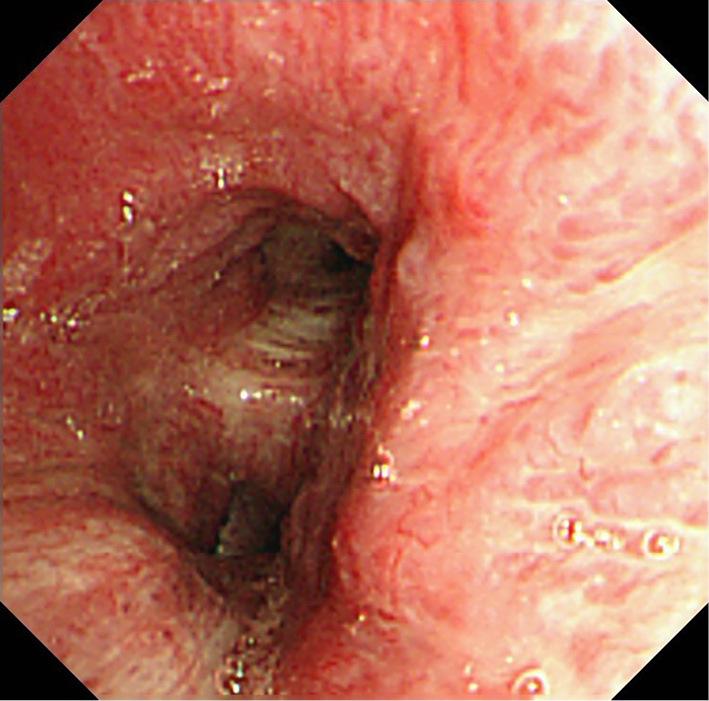

We herein report a 48-year-old man with a history of chronic atrial fibrillation (AF) and repeated hemoptysis after radiofrequency ablation. Contrast tomography showed soft tissue thickening of the left hilar region and left pulmonary vein stenosis. We performed bronchial artery embolization, but the hemoptysis did not disappear, and AF was not controlled. We performed left lung lobectomy and maze procedures since we considered surgical removal necessary as radical treatment. After the surgery, hemoptysis and atrial fibrillation did not recur. Refractory hemoptysis after catheter ablation is rare, but occasionally occurs in patients with severe pulmonary vein stenosis.

我们在此报告一例 48 岁男性,患有慢性心房颤动(AF)病史,射频消融术后反复咯血。对比断层扫描显示左肺门区软组织增厚,左肺静脉狭窄。我们进行了支气管动脉栓塞,但咯血并未消失,AF 也未得到控制。我们考虑到作为根治性治疗有必要进行手术切除,因此进行了左肺叶切除术和迷宫手术。手术后,咯血和心房颤动均未再复发。射频消融术后难治性咯血较为罕见,但在严重肺静脉狭窄患者中偶有发生。